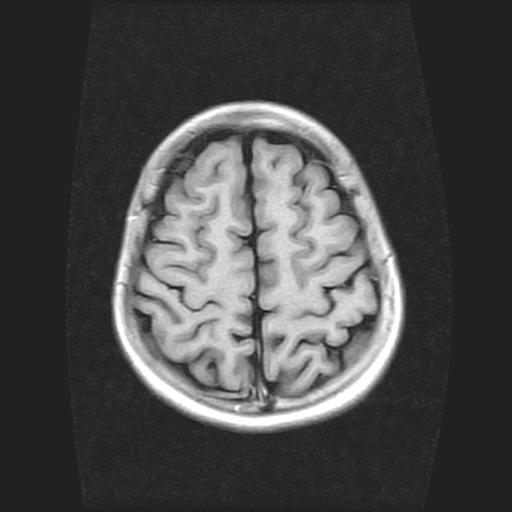

9岁女孩,三岁时诊断为癫痫,一直服丙戊酸钠,现患者一般情况良好,家长复查核磁片,看能否停药..

巨脑回

未见异常信号灶.

未发现异常信号。